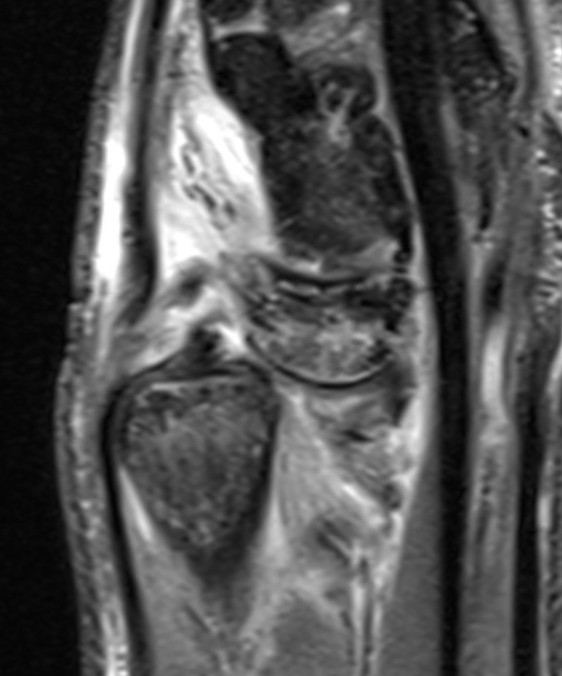

MRI

MRI demonstrating dorsal distal ulna subluxation associated with significant ligament disruption